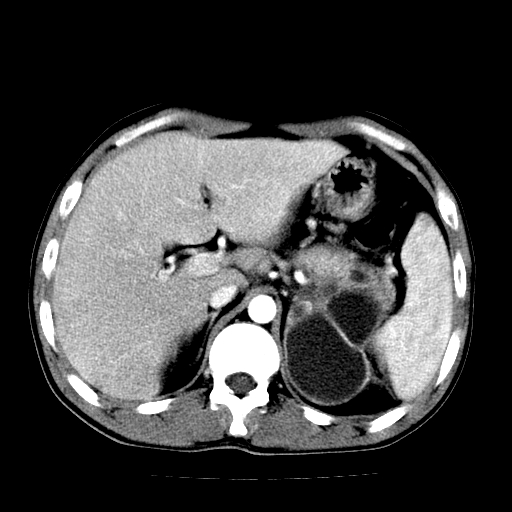

以下是引用天南地北在2007-4-30 13:36:00的发言:[br]支持慢性胰腺炎伴有假性囊肿

以下是引用andymaomao在2007-4-30 14:28:00的发言:[br]支持:1.慢性胰腺炎并假性囊肿形成可能;[br] 2.左肾形态稍增大,旋转不良。